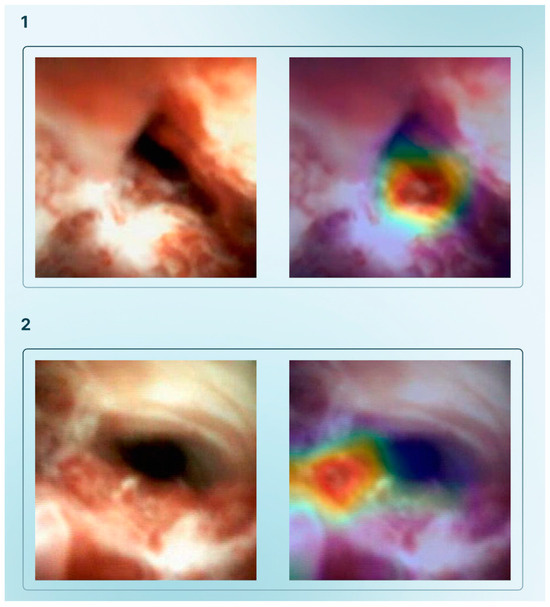

| Tonozuka et al., 2021 [27] | Detect PDAC from EUS images using a DL model | 1 | NK | 1390 static images (with data augmetation 88,320) | NK | CNN and pseudocolored heatmap | Frame labelling of all datasets (PDAC, CP, or NP) | Train–validation–test (training–validation set ratio: 90–10%; 10-fold cross–validation) | PDAC, CP, NP | 92.4% | 84.1% | 0.940 |

| Saraiva et al., 2022 [35] | Develop a CNN-based system for automatic detection of malignant BSs in DSOC images | 1 | NK | 11,855 | 9695 | Xception | Frame labeling of all datasets (normal/benign findings vs. malignant lesion) | Train–validation (80–20% with a 5-fold cross-validation) | Normal/benign vs. malignant BSs | 94.7% | 92.1% | 0.988 |